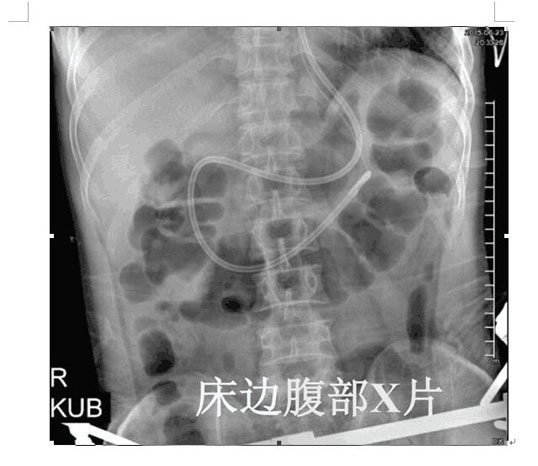

2017年4月22日,ICU成功開展了第一例床旁盲插經(jīng)鼻空腸管置入術(shù)并獲得成功。截止目前已為三位患者完成該術(shù),均為一次性盲插置管成功,臨床反映良好。此項(xiàng)技術(shù)的成功應(yīng)用,填補(bǔ)了我院在該護(hù)理技術(shù)領(lǐng)域的一項(xiàng)空白,標(biāo)志著ICU的護(hù)理技術(shù)水平邁上了一個(gè)新的臺(tái)階。

以往選擇在X線下或者使用胃鏡協(xié)助置入鼻空腸管,患者痛苦大且受輻射影響。而床旁徒手盲插經(jīng)鼻空腸管植入術(shù)是臨床護(hù)士在不依賴于其他輔助設(shè)備的情況下,通過一定的置管技巧,將管道插至十二指腸或空腸。此法省時(shí)、費(fèi)用低、操作方便、損傷小,尤其對(duì)胃蠕動(dòng)功能差的患者,不易引起食物反流、誤吸。鼻空腸管不僅可以從管內(nèi)注入營養(yǎng)液,而且還可以進(jìn)行胃腸減壓,值得臨床推廣。